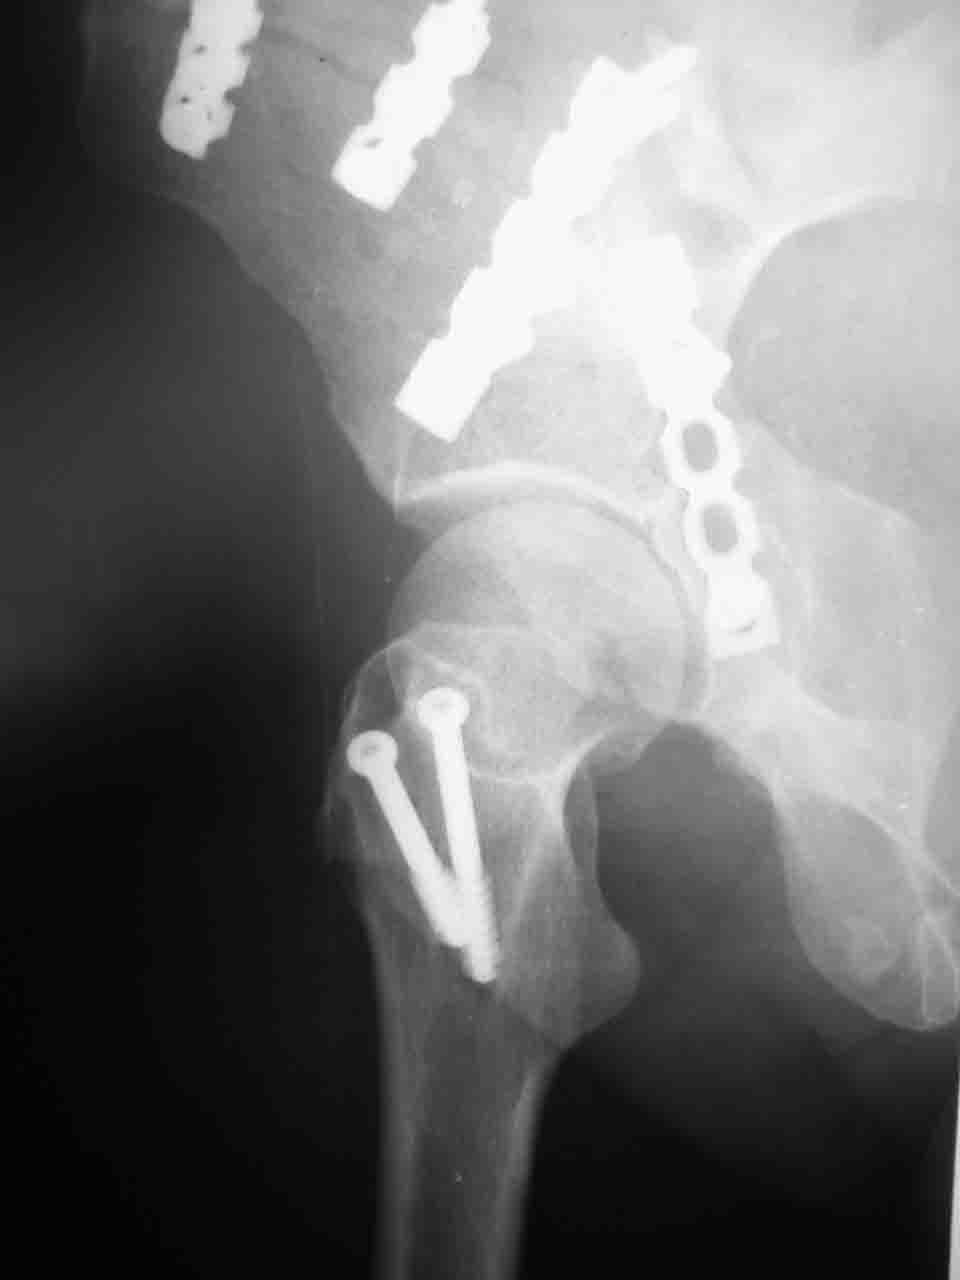

Уважаемые коллеги,43 летний мужчина, попав в автоаварию 13.10.2004, получил оскольчатый перелом обеих колонн левой вертлужной впадины.

На рентгенограммах - высокий двухколонный перелом вертлужной впадины с нарушением конгруэнтности, имеется обратная клиновидность суставной щели.

Спасибо за комментарии и рекомендации. Откровенно говоря, больного я прооперировал на прошлой неделе, через 5 дней после аварии и проблем с ним пока никаких нет, на удивление при достаточно обширной диссекции (илиофеморальный доступ) болей практически нет, так что больной самостоятельно садится в кровати, выполняет активные движения в оперированном суставе, сгибая до 60 градусов пока, далее с ассистенцией.

Причиной обращения к сообществу были возникшие непосредственно после операции сомнения и разочарования полученным качеством репозиции: а надо ли было трогать перелом вообще, репозиция передней колонны технически была очень сложна для меня, хотя реконструкции была в той же последовательности, что Д-р А.В.Рунков рекомендовал, в какой-то момент безуспешных манипуляций стал думать о *вторичной конгруэнтности*, которую не так давно обсуждали на

форуме и скелетном вытяжении. С репозицией и фиксацией задней колонны и отдельно задне-верхней стенки впадины проблем не возникло. Послеоп. Рг граммы в приложении. Если возникнут какие-либо дополнения или поправки - был бы признателен.

А какой отдел вертлужной впадины более важен передний или задний? Чем был обусловлен выбор доступа к суставу? Проще говоря, почему вы пошли передним доступом на двухколонный перелом? Мне понятны ваши сомнения, когда не удется сделать все что хотелось бы. В данном случае доступ должен быть чрезвертельным боковым (как и советовал Рунков) или двумя доступами.